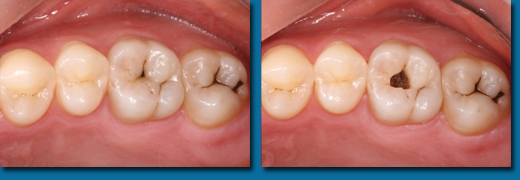

専門的にはう蝕診断といいますが一般の方が思うほど簡単なものではなく、集団検診でも歯科医院でも見逃されることが多くあります。写真の歯はいままで虫歯ではないと言われていましたが冷たいものがしみたり痛みがあったそうです。当院で調べてみると大きな虫歯が中で拡がっていることがわかりました。虫歯の入り口は小さくても中で大きく拡がっていることが多くあります。色々な診査器材を使用して虫歯も虫歯になりやすい歯も見逃しません。